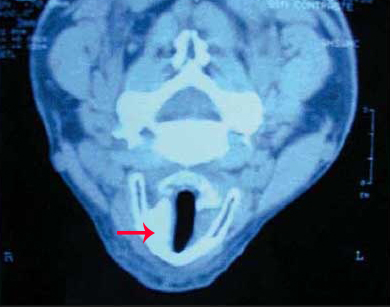

El resultado final comprobado por tomografía computerizada fue óptimo.